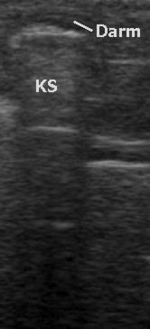

Ein häufiges Artefakt ist die Abschattung (distale Schallauslöschung) hinter stark reflektierenden Objekten mit einer vom übrigen Gewebe stark abweichenden Impedanz wie Knochen, Luft oder Konkrementen (Ablagerungen). Bei nahezu senkrechtem Schalleinfall gibt es ein starkes Echo, bei schrägem Einfall nicht.

Bei stark reflektierenden Grenzflächen kann es zu Mehrfachreflexionen (Kometenschweifartefakt, auch Ring-Down-Phänomen) beziehungsweise zu Spiegelartefakten in Form von virtuellen Bildern von vor der Grenzfläche befindlichen Objekten kommen.

Alle wasserhaltigen, blutreichen Organe sind für den Ultraschall gut untersuchbar. Schlecht untersuchbar sind alle gashaltigen oder von Knochen bedeckten Organe, zum Beispiel der Darm bei Blähungen, die Lunge, Gehirn und das Knochenmark. Manche Organe sind im Normalzustand nur schwierig, im krankhaft vergrößerten Zustand dagegen gut erkennbar (Blinddarm, Harnleiter, Nebennieren).

Das Verfahren hat in tief gelegenen Geweben eine geringere Raumauflösung als die CT und MRT. Auch die Weichteil- Kontrastauflösung kann der bei der MRT unterlegen sein. Gas und Knochen verhindern die Ausbreitung der Ultraschallwellen. Daher ist die Sonografie bei gasgefüllten Organen (Lunge, Darm) und unter Knochen (Schädel, Rückenmark) erschwert. Anders als bei anderen bildgebenden Verfahren gibt es keine standardisierte Ausbildung. Daher bestehen große qualitative Unterschiede in den diagnostischen Fähigkeiten der Anwender.